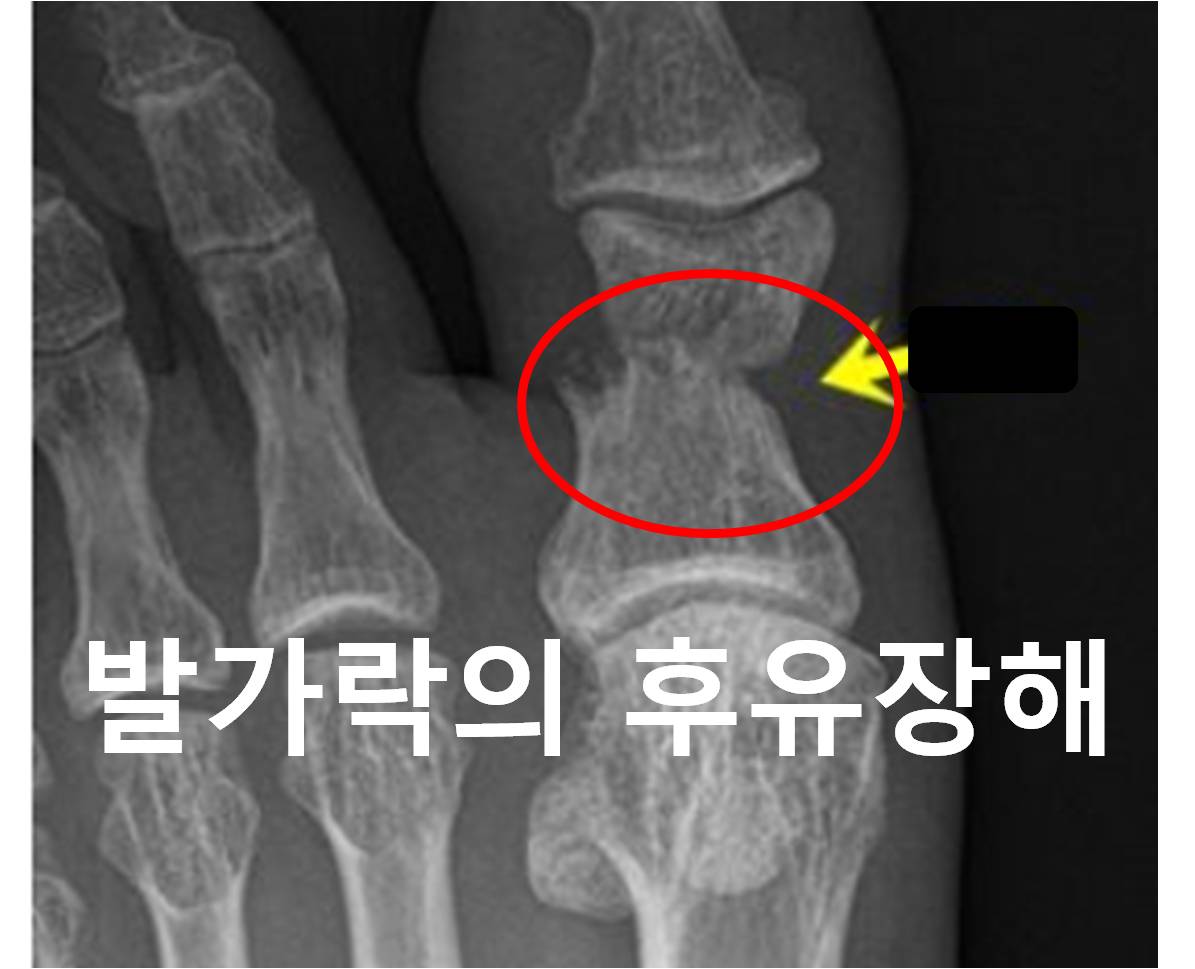

개인보험 후유장해는 총 13개 유형으로 구분하고 그 중 가장 마지막 유형이 신경계 정신행동 장해 입니다. 앞의 12개 항목의 장해는 신체 각 부위의 기능으로 평가하는 반면에, 13번째 신경계 정...